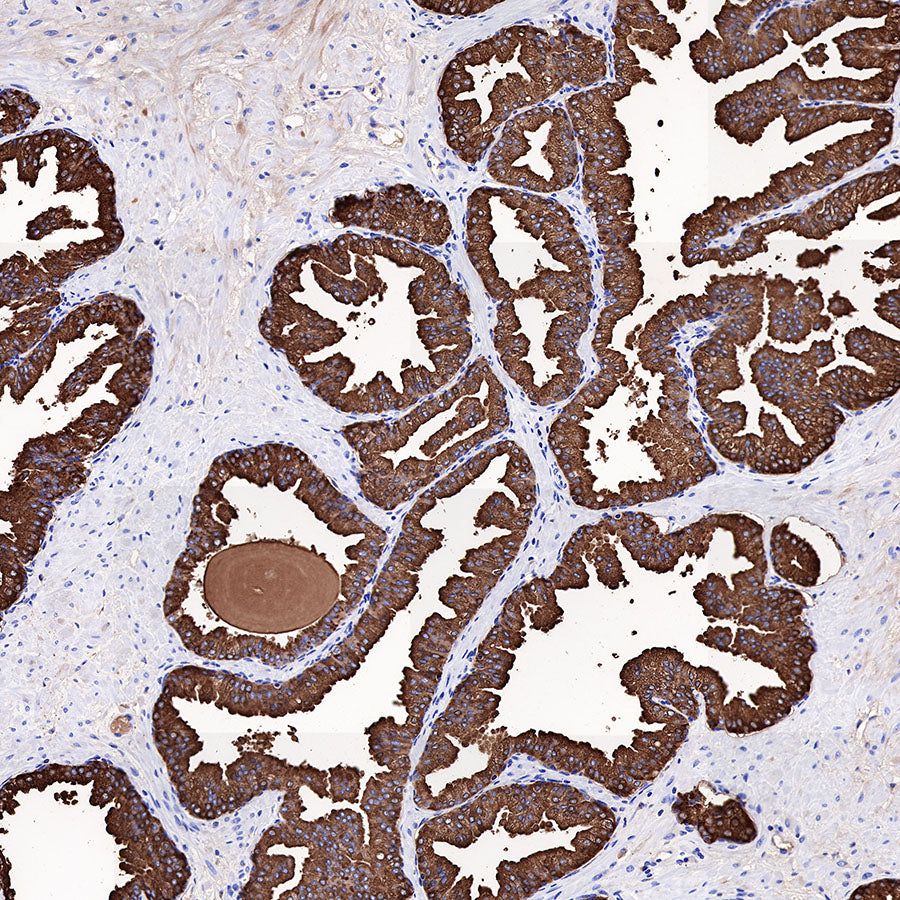

Immunohistochemistry

Negative control: IHC shows negative staining in paraffin-embedded human ovarian cancer. Anti-PSA antibody was used at 1/1000 dilution, followed by a HRP Polymer for Mouse & Rabbit IgG (ready to use). Counterstained with hematoxylin. Heat mediated antigen retrieval with Tris/EDTA buffer pH9.0 was performed before commencing with IHC staining protocol.